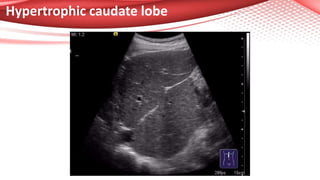

Hypertrophic caudate lobe

1. Using the classic ultrasound evaluation of the liver (assessment of

liver structure, hepatic margins, splenomegaly, caudate lobe dimensions

or signs of portal hypertension);